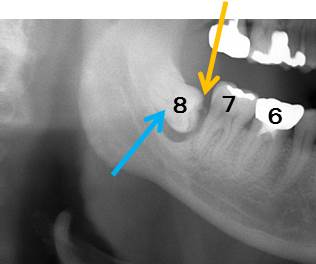

しかしながら、以下のレントゲン写真を見てください。7番の奥に水平に親知らずが向かってきています。7番の奥の歯槽骨が吸収していることが分ります。

この場合、歯周ポケットが9mm以上ありました。つまり、7の奥の歯肉の付着が喪失し、親知らずの周囲にまで感染が拡大しています。放置した場合、7番まで骨吸収が進み抜歯になってしまいます。